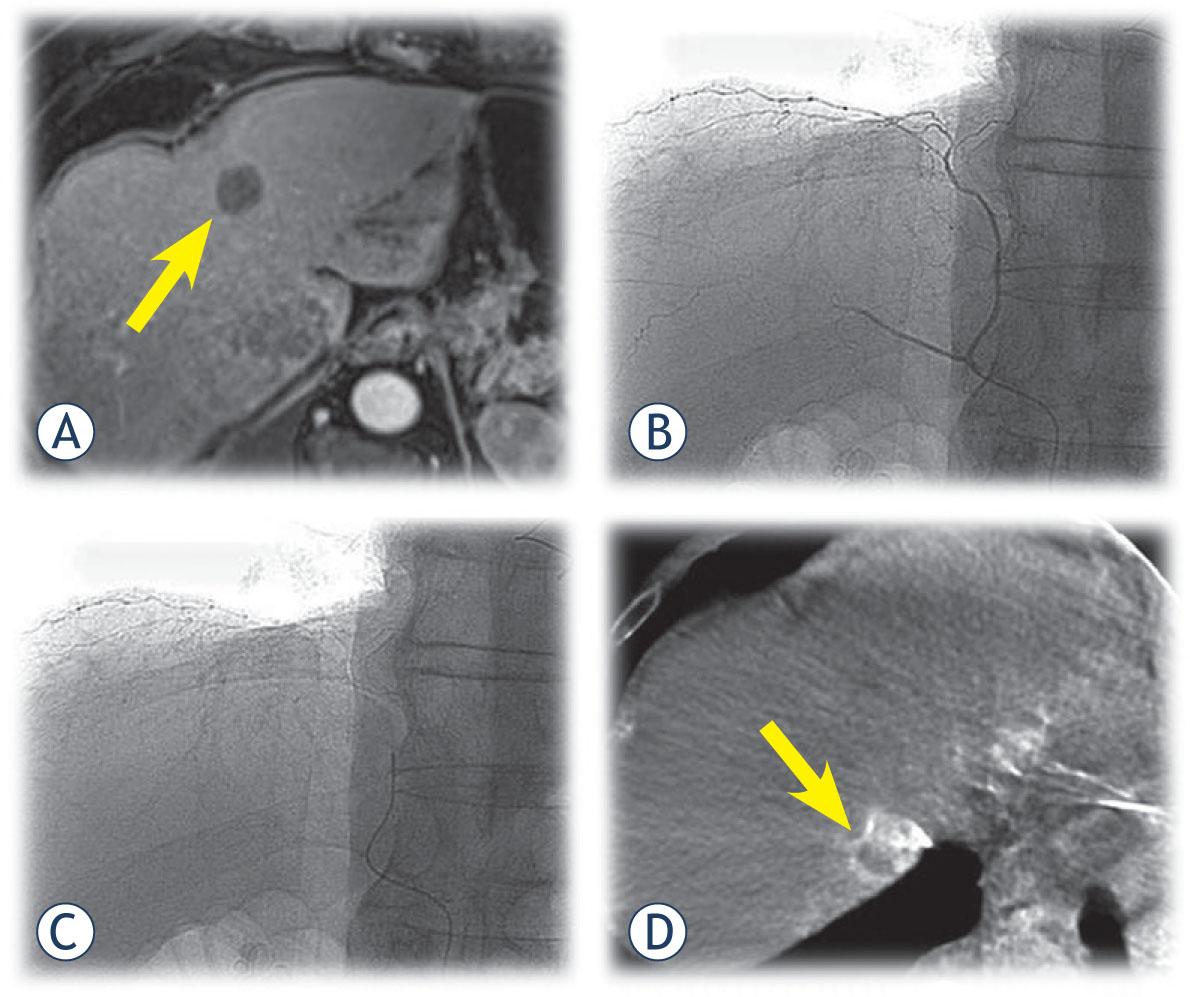

The injection rate was normally 5 mL/s with a total of 20 mL injected. A 2.4 F microcatheter (Progreat®, Terumo Europe N.V.) was then superselectively positioned in the tumor feeding arteries before delivery of the DC Bead (DEBs) (DC Bead®, Terumo Europe N.V.). Prior to DEBs delivery, DSA and CBCT were performed with the administration of iopromide through a power injector to confirm complete coverage of the targeted lesion(s). DEBs with a diameter of 100-300 μm were loaded with 50 mg of doxorubicin per vial (maximum dose of 100 mg of doxorubicin). In patients with multifocal tumors, the position of the microcatheter was changed within the same session to ensure superselective DEBs delivery in each lesion (Figure 1). Delivery of the mixture was continued until a near stasis end point or the antegrade blood flow was achieved. After DEBDOX TACE, completion arteriography was performed by manual injection to minimize reflux into non-targeted areas. All patients were kept under observation for a period of 24-48 h. Second DEBDOX TACE was performed after a period of 4-6 weeks in all patients. Additional chemoembolization procedures were performed if the multifocality of the disease did not allow for complete targeting of the tumor in the first two treatment sessions (Figure 2). DEBDOX TACE treatment was repeated on demand, that is, in patients with residual or recurrent tumors observed by CT or MRI, according to the modified Response Evaluation Criteria in Solid Tumors (mRECIST) and in agreement with recent expert opinions.22

A 64-year-old male with HCC. (A) Control MR after chemoembolization shows complete response of the target lesion (arrow) in fourth segment and partial response of the target lesion in eight segment. (B) Superselective contrast injection throught microcatheter into the righr phrenic artery. (C) Position of microcatheter prior CBCT. (D) CBCT shows that this artery suplied the target tumor in seventh segment. Superselective DEBDOX TACE was performed.